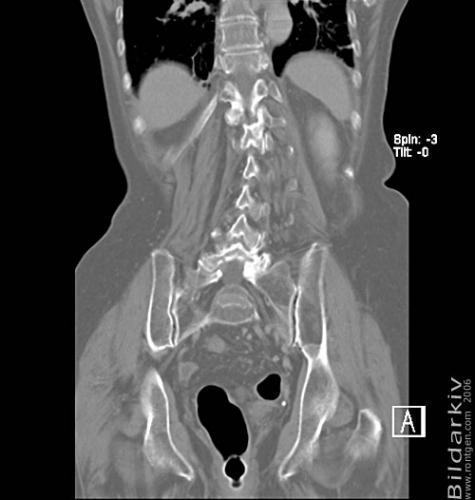

CT colon 39

Datortomografi av tjocktarmen (colon) med infunderad luft i tarmen samt med kontrast i blodbanan. Koronar bildserie.

CT multislice 16